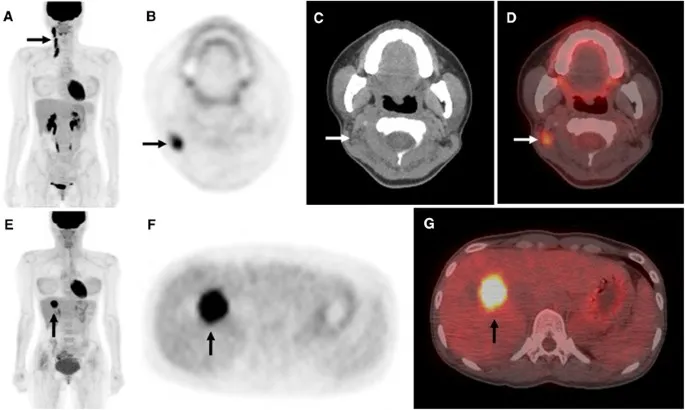

- PET-CT (FDG): Detects metabolic activity, occult recurrence, treatment response.

⭐ PET-CT can identify occult metastases or unsuspected recurrence, changing management in approximately 15-30% of patients being re-evaluated for various cancers after primary treatment.